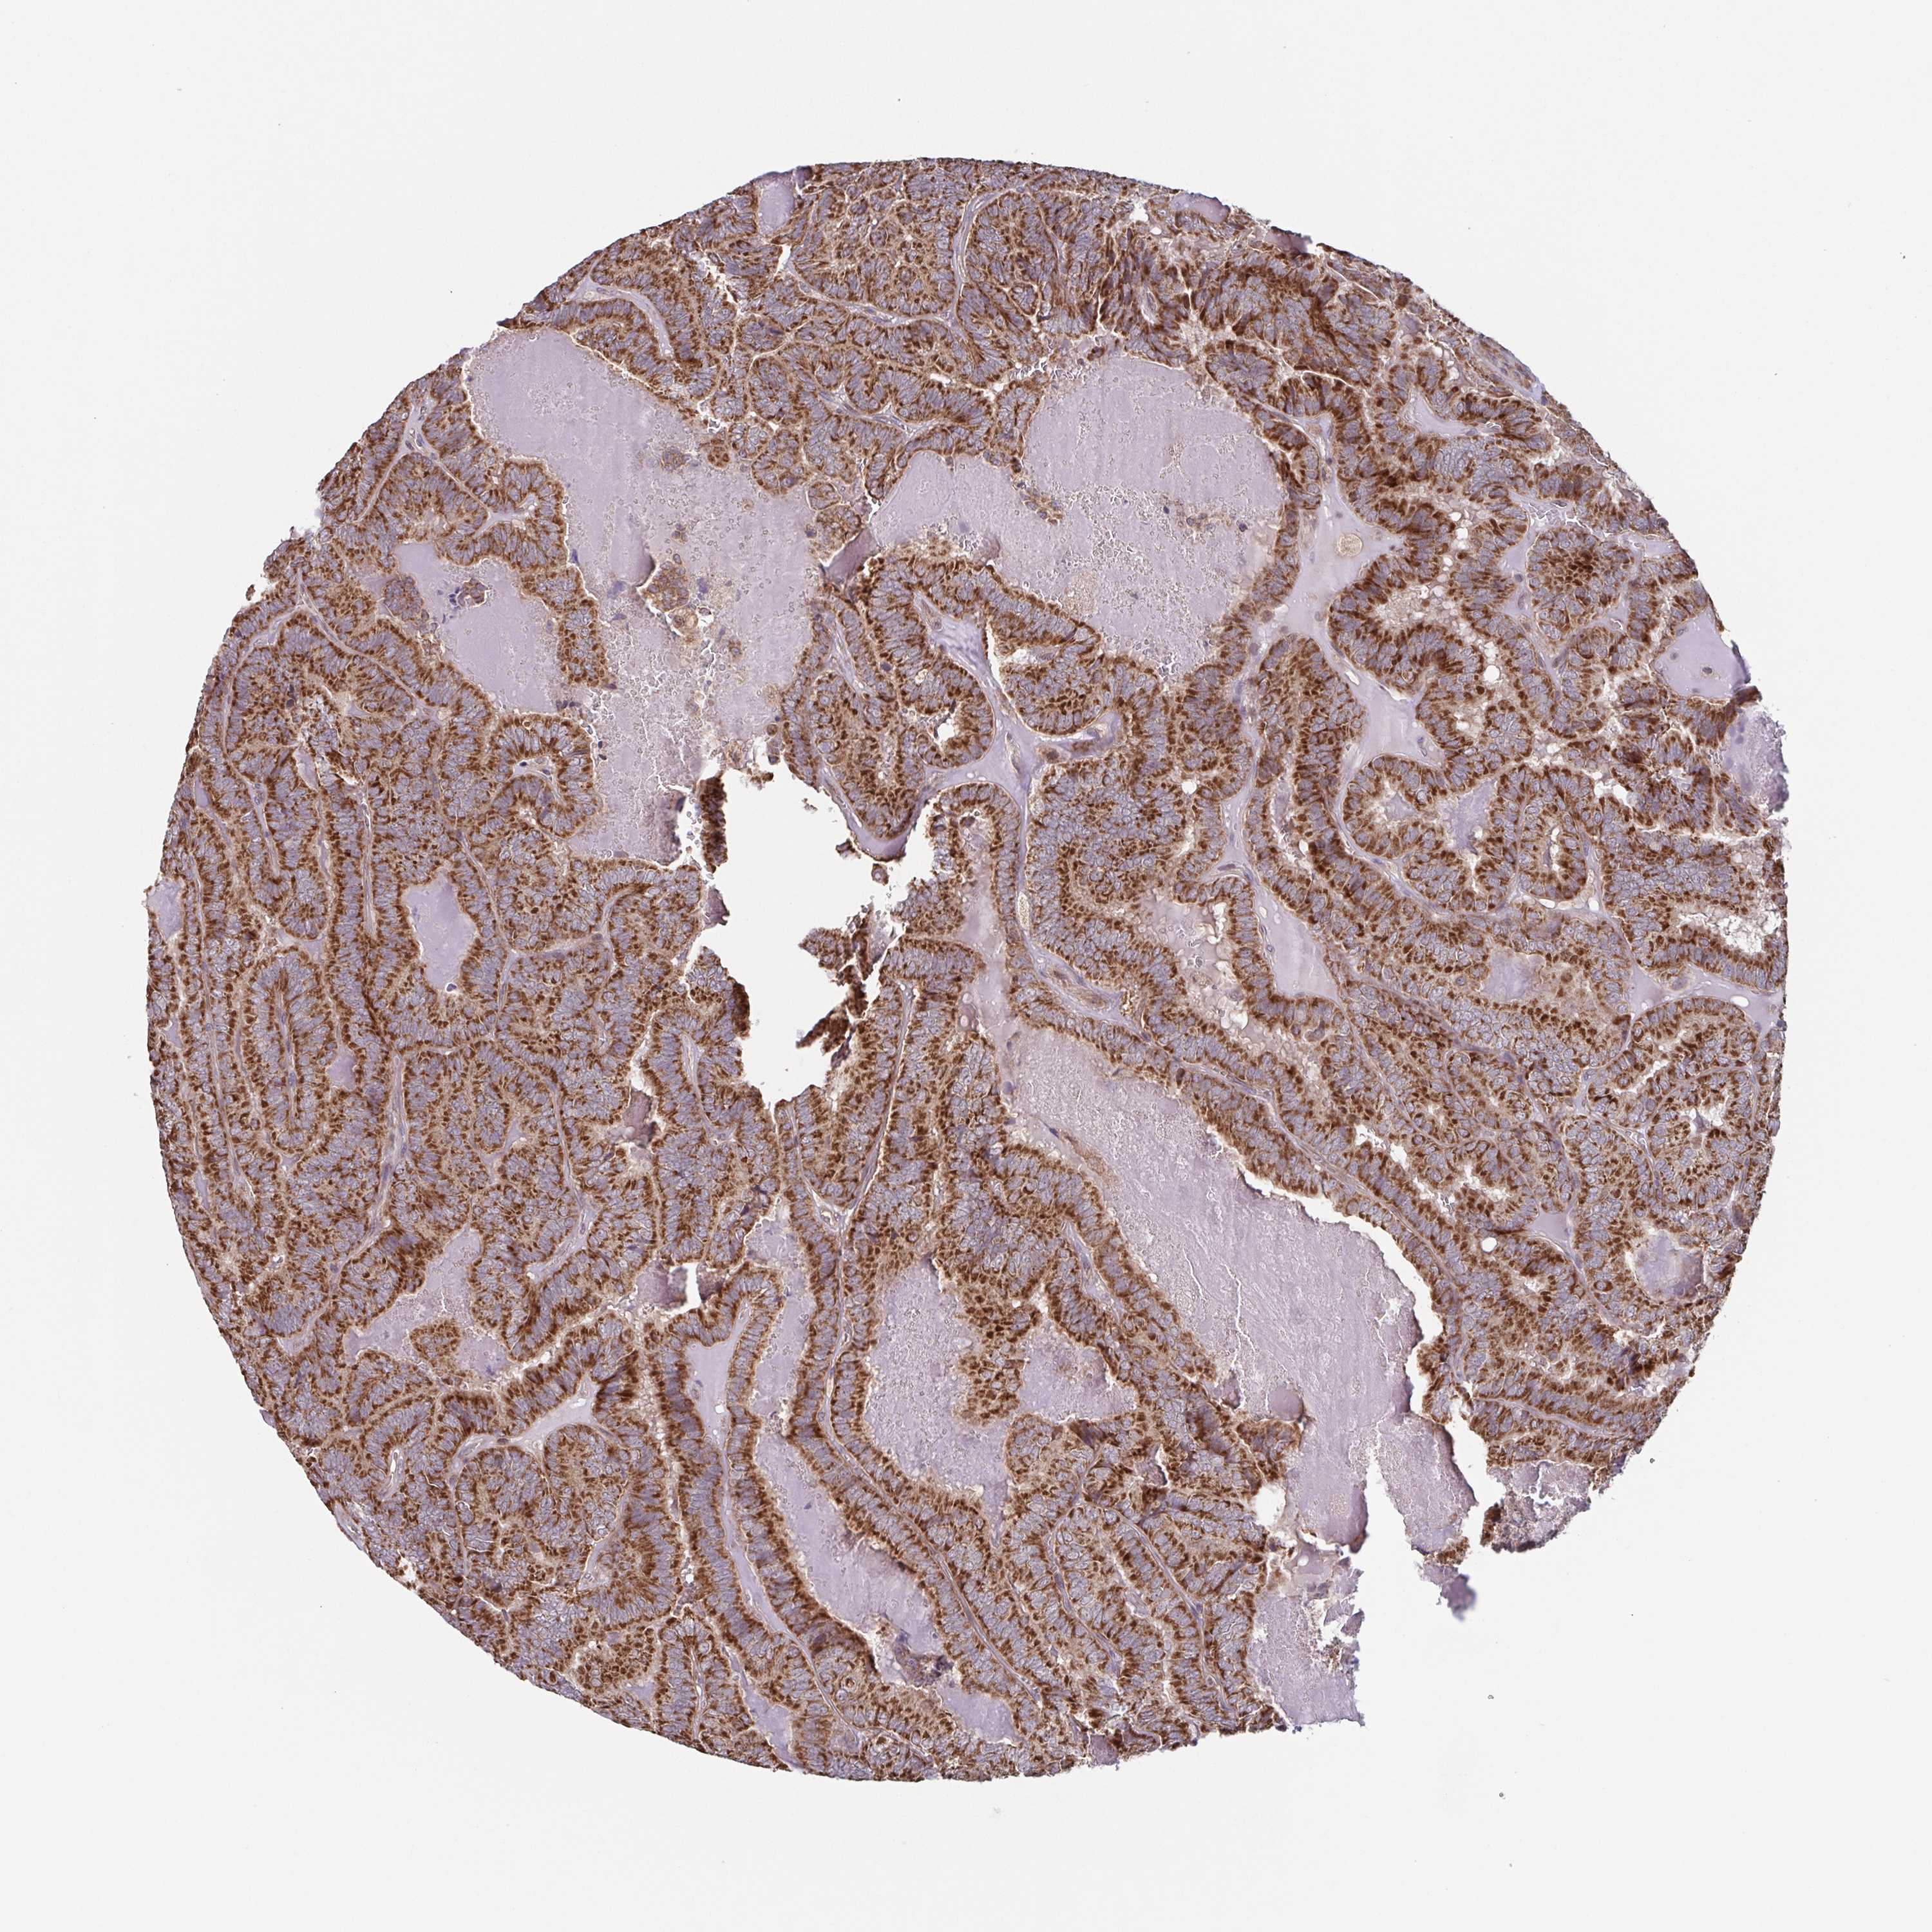

THYROID CANCER - Protein expressioni

A mouse-over function shows sample information and annotation data. Click on an image to view it in a full screen mode. Samples can be filtered based on level of antibody staining by selecting one or several of the following categories: high, medium, low and not detected. The assay and annotation is described here.

Note that samples used for immunohistochemistry by the Human Protein Atlas do not correspond to samples in the TCGA dataset.

Antibody stainingi

Antibody staining in the annotated cell types in the current human tissue is reported as not detected, low, medium, or high, based on conventional immunohistochemistry profiling in selected tissues. This score is based on the combination of the staining intensity and fraction of stained cells.

Each image is clickable and will lead to virtual microscopy that enables deeper exploration of all samples and also displays staining intensity scores, fraction scores and subcellular localization as well as patient and tissue information for each sample.

Antibody HPA023010

Antibody HPA052380

Staining

High

Medium

Low

Not detected

Intensity

Strong

Moderate

Weak

Negative

Quantity

>75%

75%-25%

<25%

None

Location

Nuclear

Cytoplasmic/membranous

Cytoplasmic/membranous,nuclear

Papillary adenocarcinoma, NOS

Follicular adenoma carcinoma, NOS